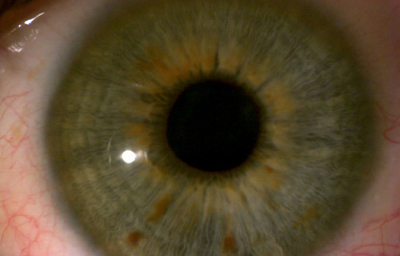

Efélides: Pueden ser una o múltiples lesiones pigmentadas planas en la superficie anterior del Iris de aproximadamente 1 o 2 mm en diámetro.

Archivo Fotográfico Dr. Carmen Barraquer

Archivo Fotográfico Dr. Carmen Barraquer

Efélides, se pueden discriminar mejor con filtro azul.

Archivo Fotográfico Dr. Carmen Barraquer